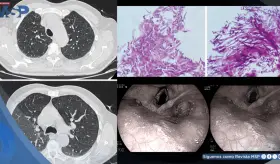

El VIH debilitó gravemente el sistema inmunológico del paciente (CD4 162), permitiendo que una bacteria poco común como Rhodococcus causara un absceso pulmonar severo que simuló tuberculosis y no respondió al tratamiento habitual.